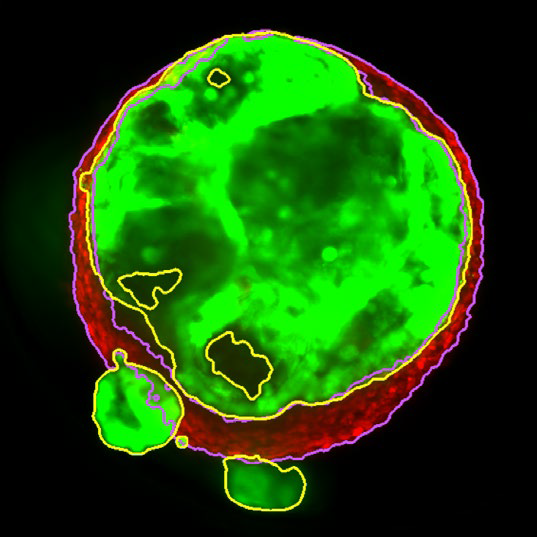

Figure 2. MaxIP image of 3D tumor co-culture microtissue - NCI-N87-GFP (gastric carcinoma; green) and NIH-RFP (murine fibroblast; red). Image Credit: Yokogawa Life Science

Figure 3. Z slice of the tumor microtissue treated with 0.05 % DMSO - tumor (yellow region) and fibroblast (purple region) are recognized separately in 3D. Image Credit: Yokogawa Life Science

Figure 4. Z slice of the tumor microtissue treated with 5 μM Lapatinib - tumor (yellow region) is decreased significantly compared to the one treated with 0.005 % DMSO. Image Credit: Yokogawa Life Science

Outcome

Tumor spheroids were created by seeding an Akura™ 384 plate with a monodispersed mixture of GFP-expressing NCI-N87 (gastric carcinoma) and RFP-expressing NIH3T3-L1 (murine fibroblast) cells, which spontaneously formed spheroids through scaffold-free self-assembly over several days. After spheroid formation, selected wells containing tumor spheroids were treated with DMSO at 0.05, 0.5, or 5.0 μM Lapatinib for six days. The images were analyzed in 3D, with NCI-N87-GFP (tumor) and NIH-RFP (fibroblast) identified separately, and the volume of each spheroid measured.